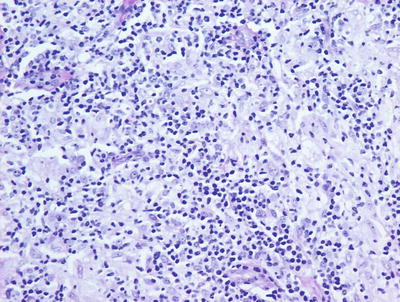

Granuloma gluteale infantum is characterized by hyperplastic epidermis with overlying parakeratosis, indicative of mild chronic external trauma. Within the epidermis , there is a mixed inflammatory infiltrate with neutrophils and eosinophils in addition to lymphocytes and histiocytes (Fig. 6.4). Abscesses containing neutrophils and/or eosinophils may be present within the dermis. Plasma cell may also be seen [8]. In well-developed cases, small granulomas resembling those seen in sarcoidosis are present, but these are not observed in the vast majority of cases [7] (Fig. 6.5). Starch granules have been observed within the granulomatous foci in some cases.

Fig. 6.4

Granuloma gluteale infantum is characterized by a diffuse dermal infiltrate of histiocytes surrounded by a mixed inflammatory infiltrate

Fig. 6.5

Sarcoidal-type granulomas admixed with lymphocytes and scattered neutrophils are observed in well-formed lesions of granuloma gluteale infantum